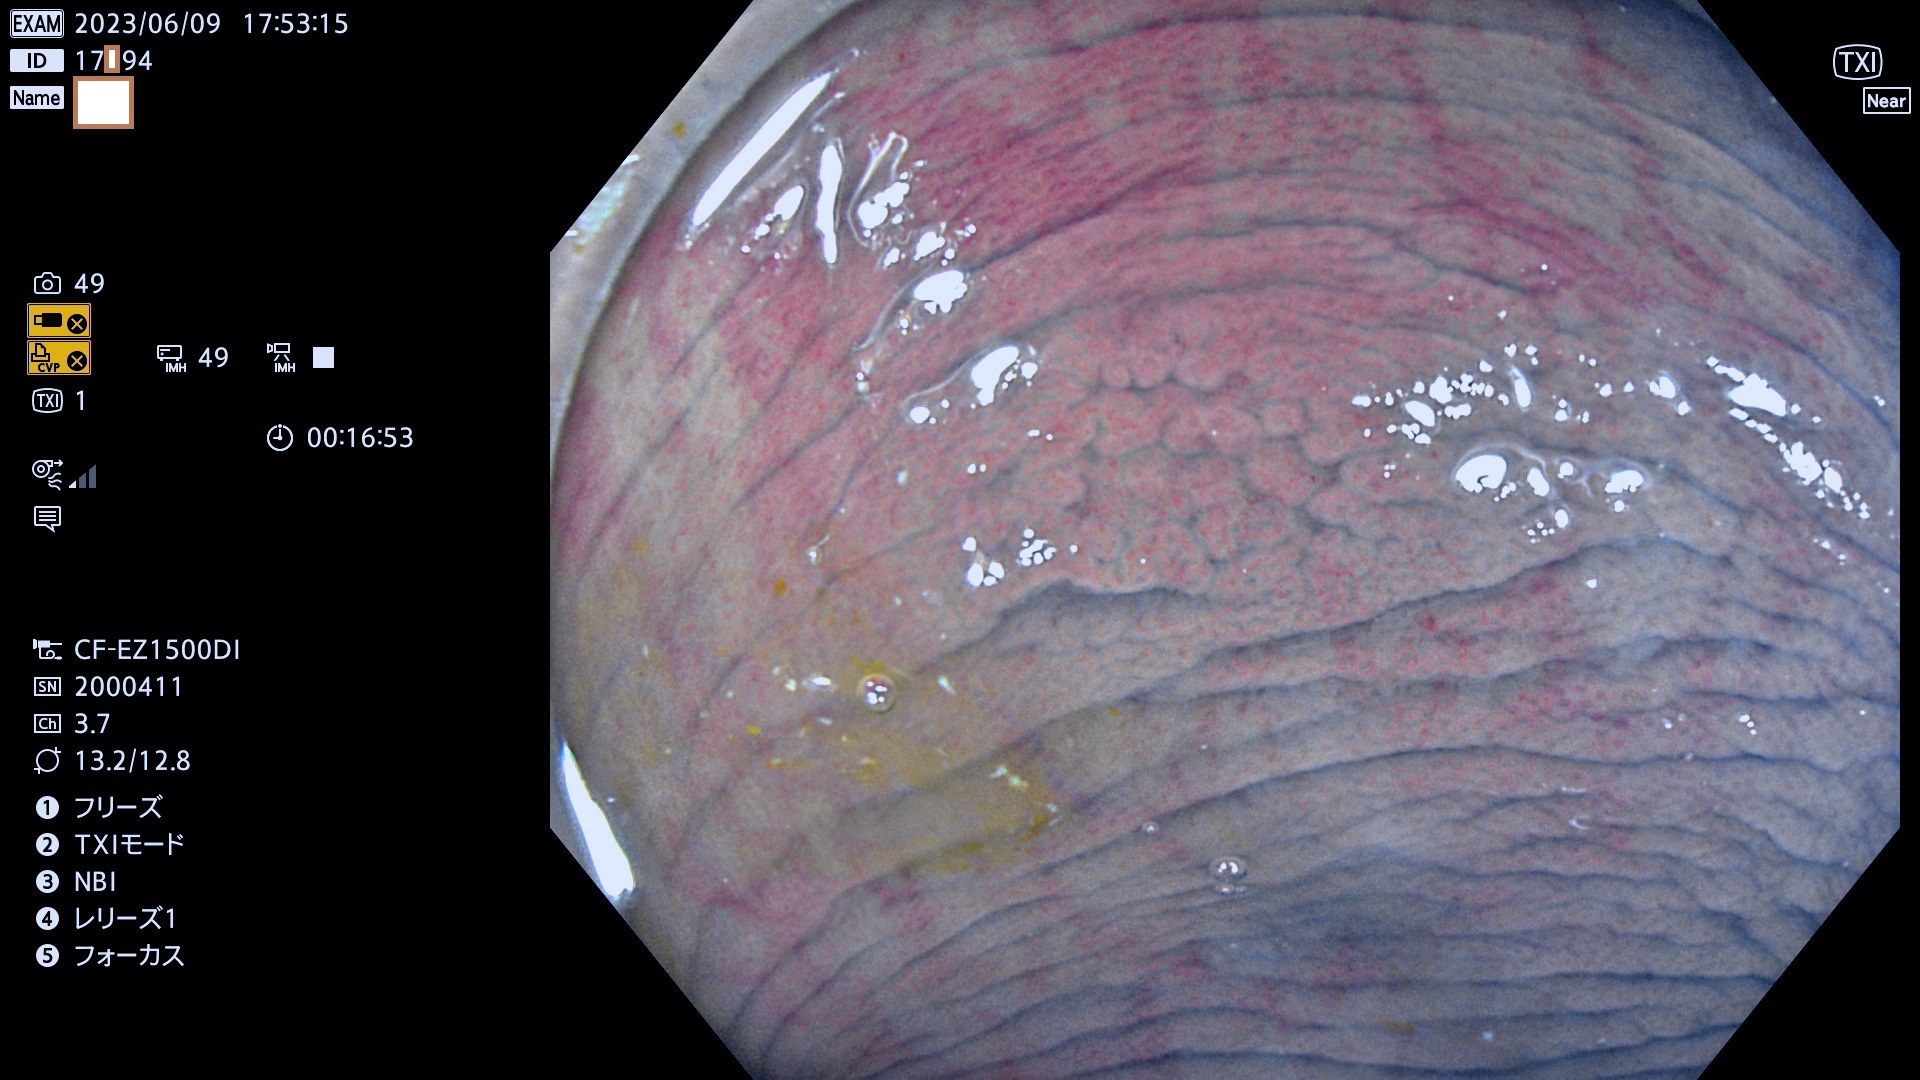

「表面型腫瘍」の中で、完全に平坦な物をUb、陥凹している物をUcと呼びます。平坦隆起型(Ua)よりも、発見が難しく危険な病変です。このタイプの発見率は「腺腫発見率」よりも、遥かに重要な意義があります。

毎週の検査(木・金・土・日)に当院の検査で発見されたUb、Uc病変を、その週の日曜の夜にUPし1週間、提示します。

抽出の対象期間 2023年6月8日(木)〜11(日)の4日間(48件の検査)